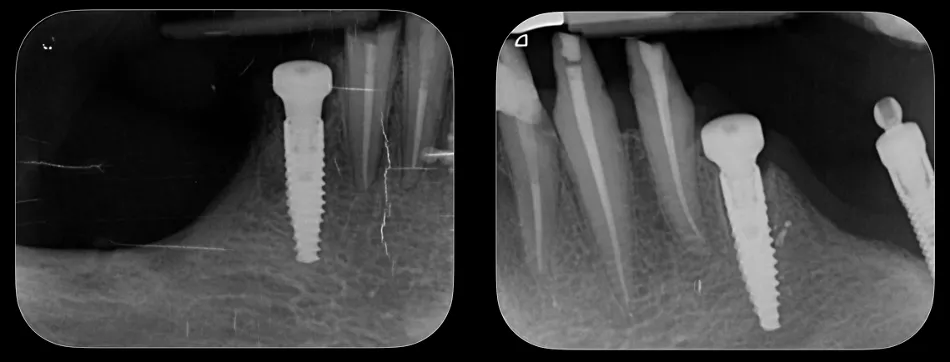

Implant placement was performed using Straumann® BLC™ implants: a Ø 3.3 mm Regular Base, 12 mm SLActive® implant at site 34 and a Ø 3.3 mm Regular Base, 10 mm SLActive® implant at site 43 (Fig. 47).

Fig. 47

Dental bone grafting material was used for GBR in the post-extractive implant sites 34 and 43.

Healing abutments were placed, and primary stability of the implants was confirmed. Postoperative evaluation after immediate flapless implant placement showed stable soft tissues at the surgical sites, with minimal trauma observed (Fig. 48).

Postoperative radiographs of the lower jaw were taken following implant placement, confirming proper positioning and angulation of the implants (Fig. 49).

The healing screws in the lower jaw were removed and replaced with straight (0°) Novaloc® abutments, preparing the implants for the next stage of prosthetic restoration (Fig. 55).

X-rays taken at this stage showed the precise positioning of Novaloc® abutments (Fig. 56).